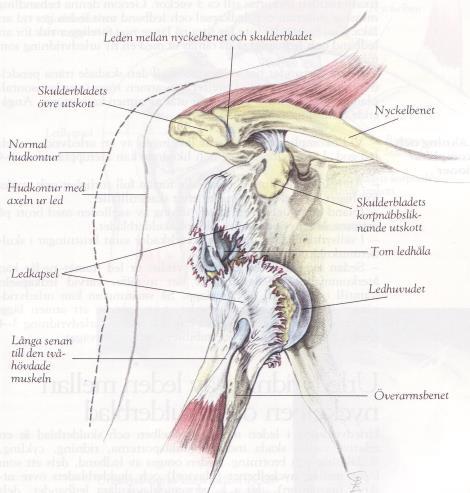

Skjer oftest fremover (90-95%), fordi det først og fremst er muskler som hindrer at leddhodet forskyves

Normal struktur i skulder To bilder av fremre luksasjon. Bilder tilpasset av Therese Dahl Kristensen

AC-luksasjon (acromioclavicularleddet):

• Hel eller delvis avrivning av leddbånd mellom ytre del av krageben og benets utspring på skulderbladet • Opptrer ofte ved fall hvor man lander direkte på skulder, f. eks sykkel eller motorsport • Kan være vanskelig å skille fra brudd i ytre del av kragebenet eller skulder ute av ledd.

Tegn på luksasjon, brudd eller muskelavrivning: • Feilstilling/forkorting av armen kan forekomme, f.eks. «trappetrinn» • Overarmen kan være vridd utover (95 % av luksasjonene skjer fremover) • Overarmen kan henge rett ned • Smerter direkte over AC-leddet • Smerter, mest i skadeøyeblikket, kan avta noe etter hvert ved helt avrevet muskel • Avrevet biceps kan se ut som en ”Skipper’n-muskel” (tydelig ”kul”) Andre generelle tegn og symptomer på skade: • Pasienten holder ofte armen inn mot kroppen • Nedsatt funksjon • Kan få hevelse over skadestedet • Smerter ved bevegelse (om man klarer å bevege armen)

Inspeksjon: Se etter sikre bruddtegn og hevelse, vurder sidelikhet. Ved skulder ute av ledd kan man se trappetrinn i skulderen.